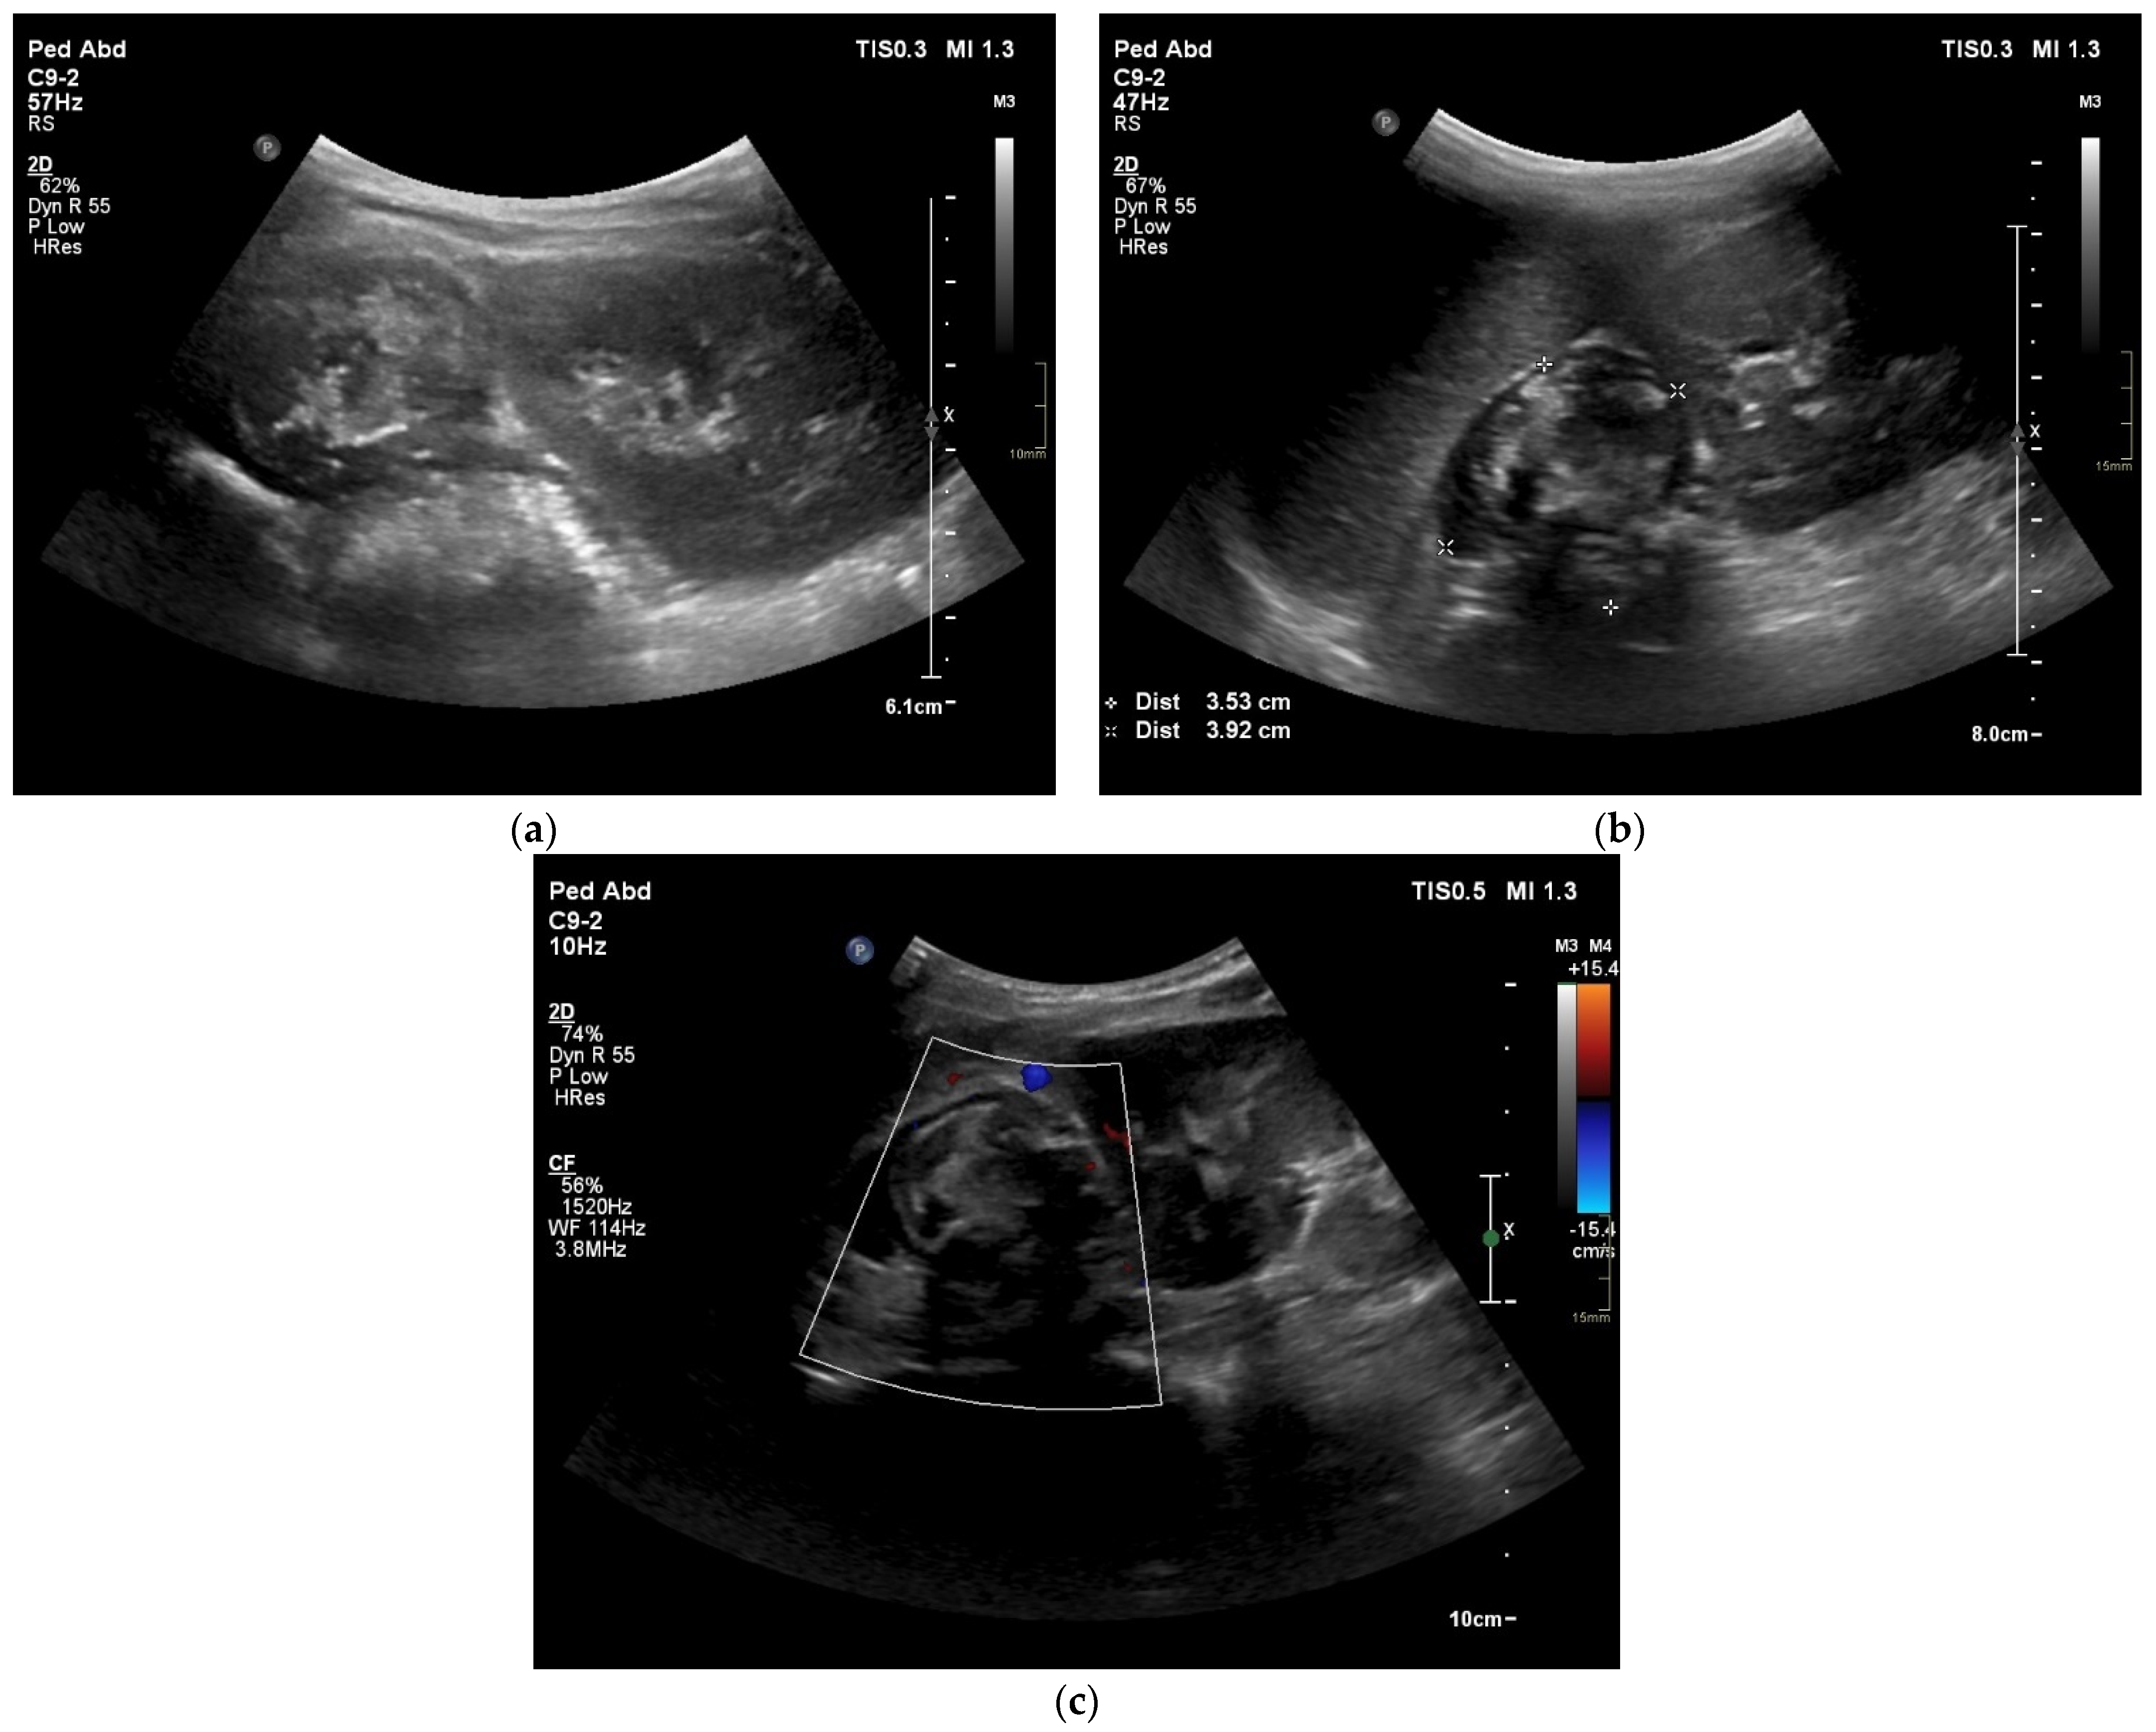

4. Case Presentation